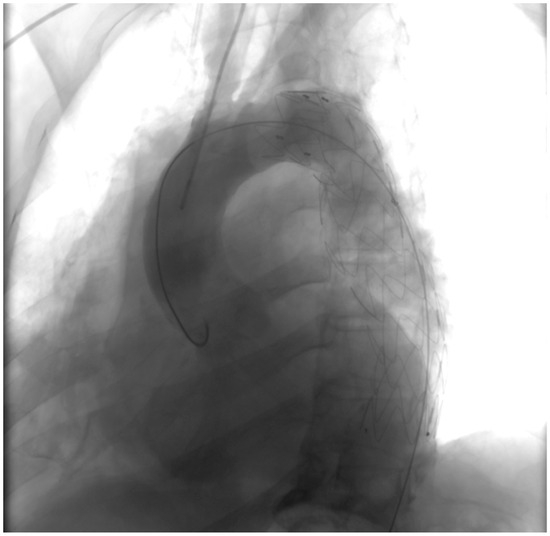

- Right pleural aortic false aneurysm (Figure 3): The most striking feature was the presence of an expansive false aneurysm within the right pleural cavity, measuring approximately 12.92 cm × 9.3 cm. The size and location of this pseudoaneurysm were unprecedented, introducing a challenge in terms of diagnosis and intervention.